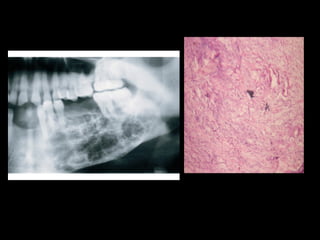

1. Radiographic evaluation, OPG shows multilocular

radiolucency with root resorption and

displacement of teeth

4. Incisional biospy, shows typical pallisaded

columnar cells resembling ameloblasts.